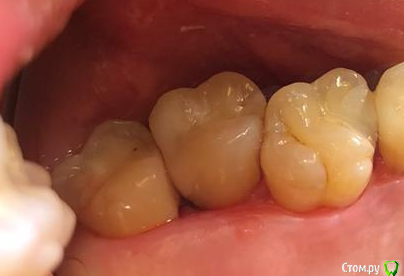

apex007 Опубликовано 26 января, 2021 Поделиться Опубликовано 26 января, 2021 Добрый день! 27 и 28 зубы немного развернуты в сторону щеки . В 27 серьезные разрушения со стороны 28, на уровне десны и под десну . Между 27 и 28 глубокий карман, видимо, из-за попадания остатков пищи в карман и возник кариес 27. Сейчас 27 вскрыт, врач предлагает удалить 28, чтобы можно было немного оттеснить десну и восстановить дистальную стенку 27. При этом 27 пришлось депульпировать, сейчас каналы еще не закрыты. Правильно понимаю, что удаление 28 приведет к ускорению рецессии кости и ухудшению прогноза для 27? Следует ли удалять 28 сейчас или восстановить 27 как получится и посмотреть на результаты эндодонтии через год (в 27 сложные каналы ), а карман промывать ирригатором? Фото по состоянию до начала лечения. Ссылка на комментарий